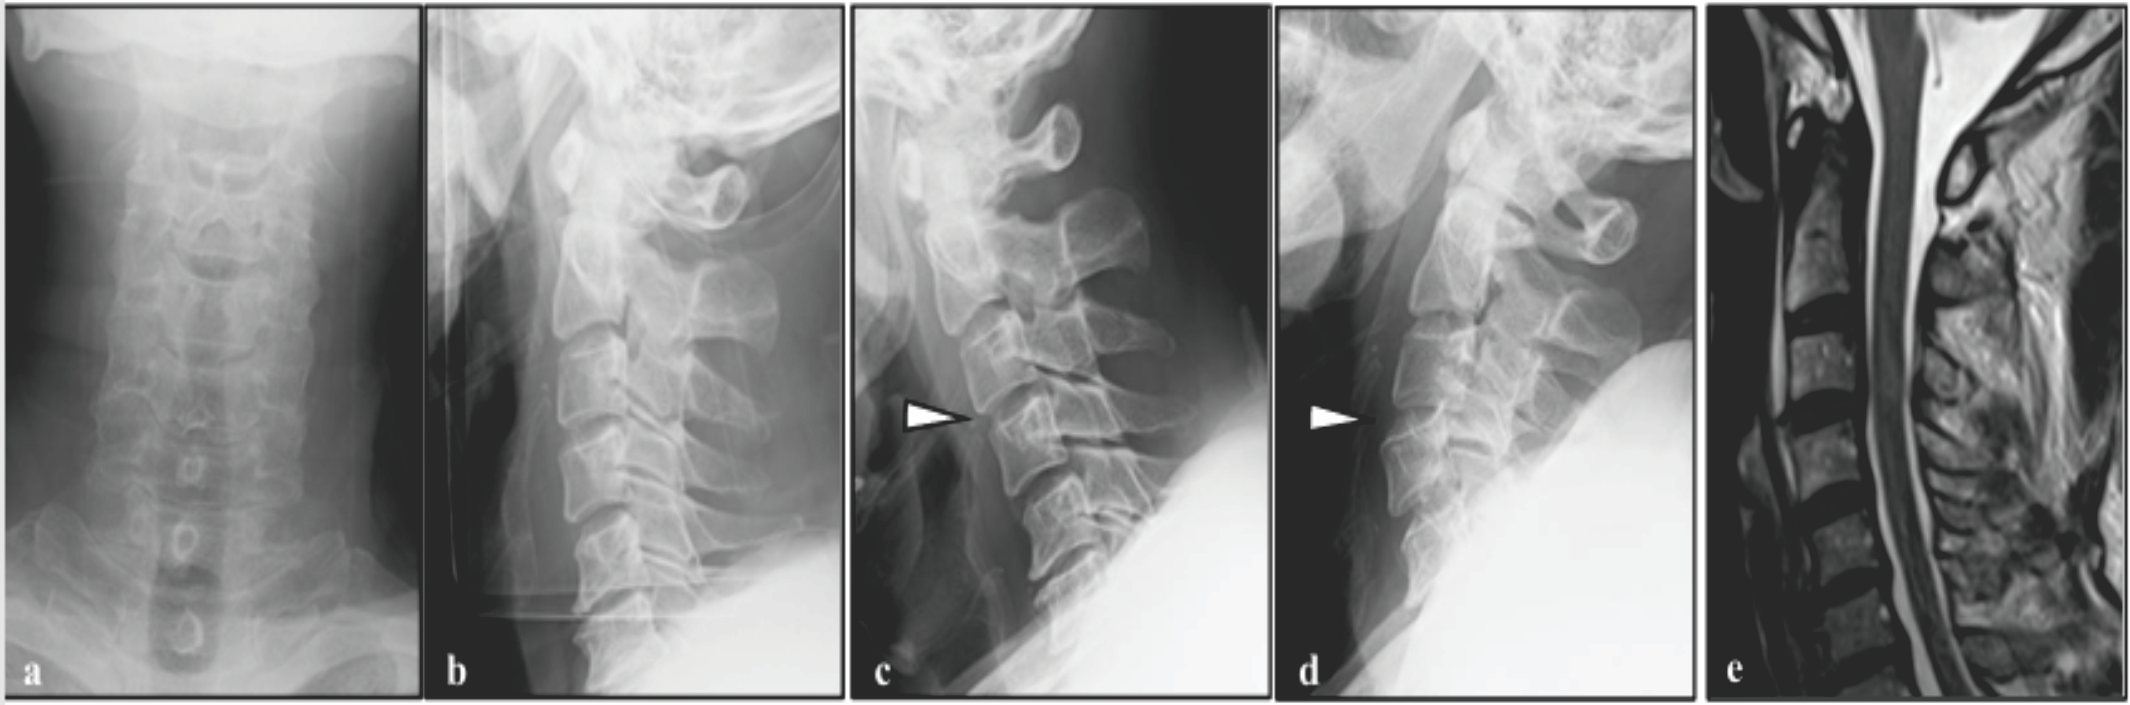

Pseudomeningocele Presenting with Neurological Symptoms 1 Year after Spinal Surgery: A Case Report

Shintaro Yamamoto , Ryunosuke Fukushi , Tomonori Morita , Arihiko Tsukamoto , Shutaro Fujimoto , Atsushi Teramoto

………………………………p.163-167